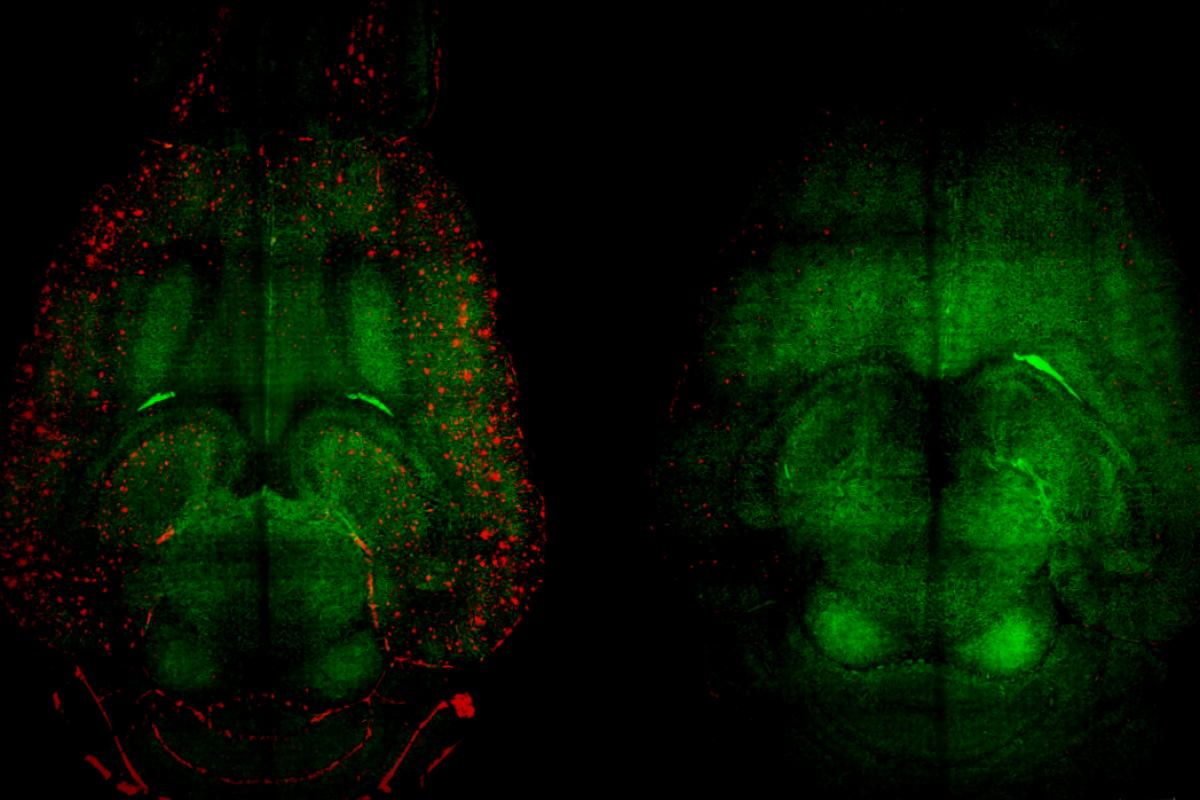

If there are too few keys, the particles would falter. Too many, however, would blur the line with sticky amyloid plaques, potentially causing issues. Ultimately, they affixed 40 keys per particle and proceeded to test on mice with significant amyloid-beta build-up, particularly a group bred for rapid Alzheimer’s development (APP/PS1 mice)—these older mice exhibited pronounced cognitive deterioration. They received one dose of the treatment.

Remarkably, by two hours post-injection, Aβ concentrations diminished by almost 45%.

The drop wasn’t just limited to the brain; increasing levels were observed in the bloodstream, marking a vital indication that the toxic plaques were indeed being expelled from the brain for elimination. The decrease in Aβ from the brain correlated perfectly with the excess found in the blood.